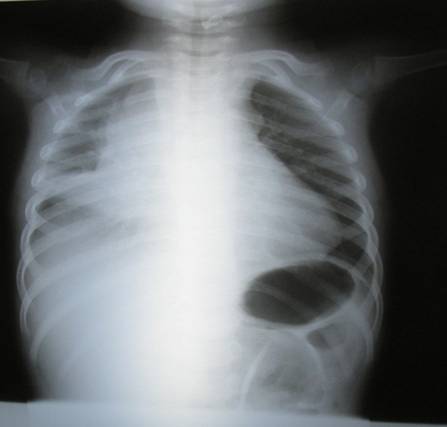

Ecocardiograma transtorácico: que informa compresión y desplazamiento de cavidades derechas por una tumoración mediastínica 39 x 48 mm acompañado de derrame pericárdico de 12mm sin compromiso hemodinámico significativo. Dados estos hallazgos se solicita Tomografía tóraco-abdominal de urgencia (Figura 2) que informa: voluminosa tumoración mediastínica sólida, heterogénea con áreas de necrosis, que ocupa mediastino anterior y medio, extendiéndose desde el nivel de T2-3 hasta el diafragma.

Figura 2: TC (superior e inferior), que muestra gran masa mediastinal anterior y sus relaciones con grandes vasos y vía aérea.

La misma, ocupa el espacio pre-vascular y para-traqueal derecho, comprimiendo levemente la tráquea y el bronquio fuente derecho. En su sector anterior no se delimita claramente del timo, observándose la arteria pulmonar derecha sin compresión, pero no identificándose la vena cava superior. En su sector inferior, se extiende rodeando las cavidades cardíacas derechas que aparecen distorsionadas por la tumoración y sin plano de separación con ésta. Se observa derrame pericárdico, acompañado de derrame pleural moderado a derecha. Abdomen sin particularidades. Valorada por equipo de oncología se decide su traslado a centro de hemato-oncología pediátrica, para completar valoración e iniciar tratamiento neoadyuvante. De la paraclínica, se destaca una AFP de 17444 mcg/ml., por lo que se hace diagnóstico de tumor de células germinales de saco vitelino (yolksac) mediastinal, con derrame pleural y pericárdico, estadio 4. Se coloca port-a-cath y se comienza con series de poliquimioterapia con buena evolución clínica y humoral, con disminución de la AFP a valores de 37,9 mcg/ml. Se realiza ecocardiograma y tomografía de control que evidencian reducción de la masa tumoral, sin compresión de cavidades cardíacas. Dada la buena evolución, se decide en ateneo multidisciplinario su resección quirúrgica. Preoperatorio inmediato: se colocó una vía venosa periférica 20 G en el territorio de la vena cava inferior, monitorización estándar de la ASA.